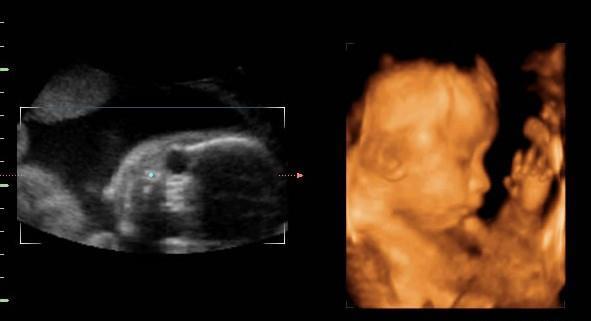

四维彩超的主要目的是大排畸,排查胎儿有无畸形,在检查的时候,为了更清晰的看到胎儿各部位发育情况,排查胎儿的畸形,他们会选择能够清晰观察胎儿的角度拍摄,而不是怎么好看怎么拍。拍摄的时候很可能因为角度问题,把胎儿的面部拍的扁平,鼻子嘴巴又大又扁的。

四维彩超拍摄的照片,只是胎儿的一个大概影像,并不能跟专业的相机来做对比。首先,拍摄的时候,胎儿泡在羊水中,在羊水的作用下,拍摄的照片会有些变形;其次,胎儿可能不是出于静止状态,有些胎儿可能在打嗝,有些胎儿可能在乱晃,这些不静止的行为,都会影响照片的拍摄;最后,四维彩超的目的是为了排查胎儿畸形,在拍摄的时候,为了更清晰的观察胎儿发育,可能会对局部进行放大。这三种情况,都会导致胎儿的照片鼻子大嘴巴大,看起来丑巴巴的。